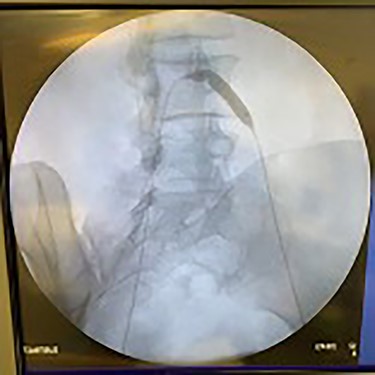

Catheter arteriogram results showed significant occlusion of the left iliac artery (Figs 3 and 4), the right iliac artery (Fig. 1), as well as the distal abdominal aorta (Fig. 2). There were numerous collateral vessels noted, indicating the presence of long-standing proximal stenosis (Fig. 1). The decision was made to use angioplasty to help widen the areas of stenosis. An 8 mm × 40 mm Passeo balloon was advanced from the right femoral artery into the left iliac artery (Fig. 7) and insufflated to 6 mmHg (Fig. 6). The balloon was allowed to remain expanded for 1 min and then was deflated. Next, the distal aorta was repaired in a similar fashion. The balloon was advanced into the distal aorta from the right femoral access and insufflated to 12 mmHg (Fig. 8). The balloon was allowed to remain expanded for 90 s.

Fluoroscopy showing dilation of the distal aorta post-angioplasty.